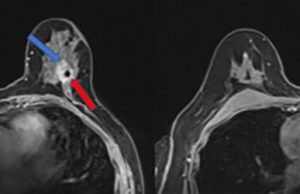

Cancro al seno: fare prevenzione con uno screening personalizzato

Uno studio pionieristico ha valutato un approccio personalizzato allo screening del cancro al seno che valuti il rischio delle pazienti, anziché eseguire automaticamente mammografie...